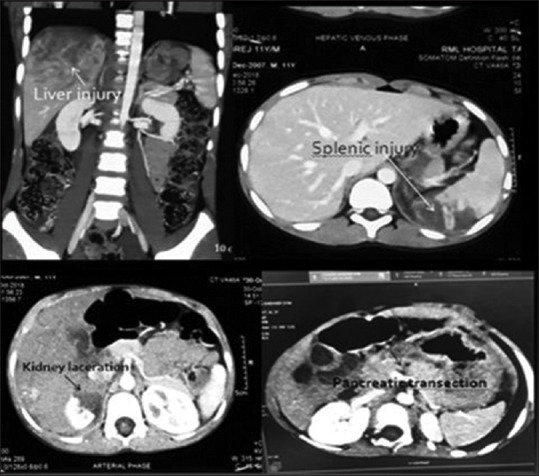

Results: A total of 68 patients were included in the study. Fall from height was the most common mode of injury (62%) followed by road traffic accidents (35%) and the other causes included in the miscellaneous group (hit by animal and fall of heavy object on the abdomen; 3%). Most commonly injured organ was liver (n = 28, 41%) followed by spleen (n = 18, 26%) and kidney (n = 15, 22%). Other injuries were bowel perforations (jejunal [n = 4], ileal [n = 1] and large bowel [n = 1]; 9%), pancreaticoduodenal (n = 5, 7%), urinary bladder (n = 3, 4%), abdominal vascular injury (iliac vein-1, inferior vena cava-1;3%), adrenal haematoma (n = 2,3%) and common bile duct (CBD) injury (n = 1, 1%). More than one organ injury was seen in 13 cases (19%). Non-operative management was successful in 84% (n = 27) and laparotomy was done in 16% (n = 11). Most of the patients sustained Grade IV injury (n = 36, 53%) and majority of the patients (n = 60, 88%) had good outcome without any long-term complications.

Conclusion: Profile of paediatric blunt abdominal trauma include solid organ injuries such as liver, spleen, kidney, pancreas, adrenal gland and others like bowel injury, CBD, urinary bladder and abdominal vascular injury. The grade of injury does not correlate with the outcome in a higher grade of injury and these children had good outcome.